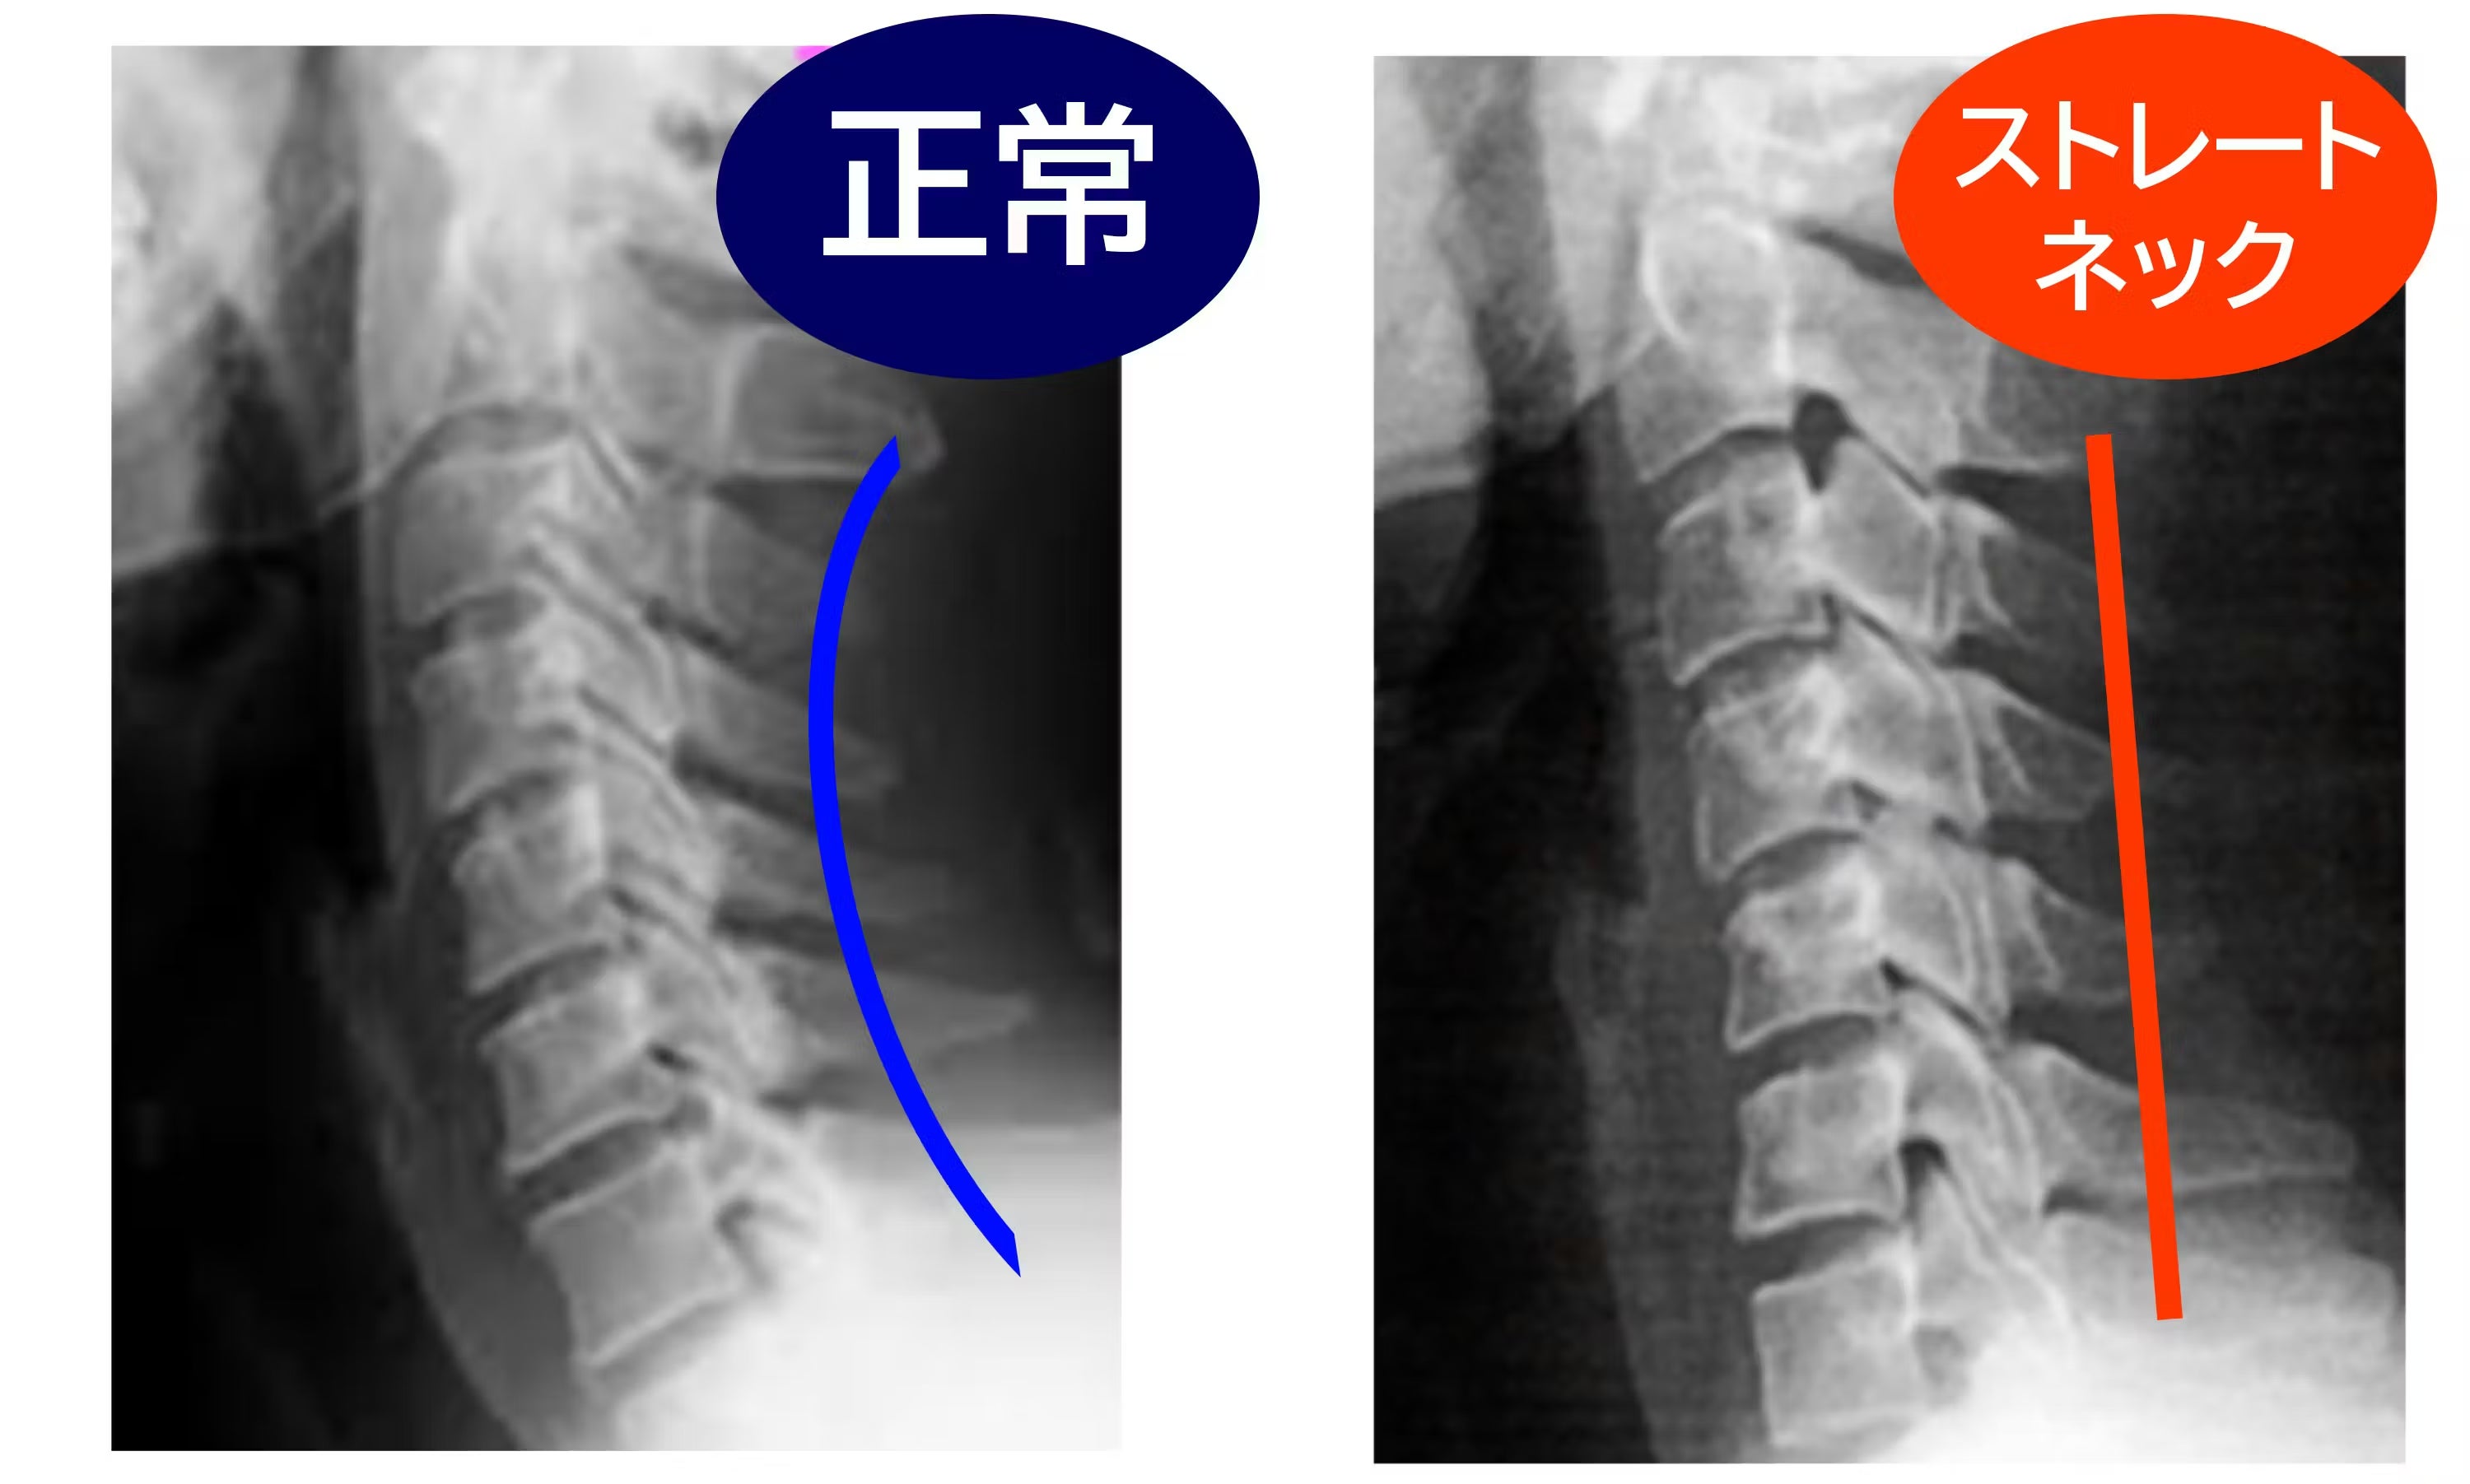

長時間のスマホ操作やデスクワークで、私たちの首は前に突き出しがちです。その状態が続くと、本来S字を描くはずの頸椎の自然な湾曲(カーブ)**失われ、いわゆる「ストレートネック」のような姿勢に。

肩や首の違和感、頭まわりの重さ、姿勢の乱れなどにつながることもあります。独自のアーチ構造が背中全体をやさしく押し上げ、首を下から支えながら、頸椎を理想的なカーブへと導きます。